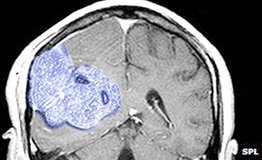

Tế bào gốc giúp bảo vệ mô khỏe mạnh trong quá trình xạ trị